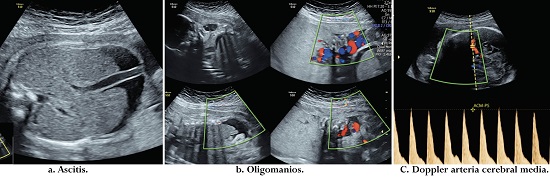

Examen físico: frecuencia cardiaca 78 latidos por minuto (lpm), presión arterial 105/ 60 mmHg. Altura uterina de 25 cm y fetocardia 149 lpm. Hallazgos positivos: altura uterina de 26 cm y fetocardia 139 latidos por minuto (LPM). Se toman paraclínicos: hemograma normal: Hb: 11 mg/ dl, creatinina: 0.5 mg/ dl. Hepatitis B: negativo, prueba VIH: negativa, prueba treponémica rápida: positiva, prueba no treponémica (VDRL) positiva en 1: 64 diluciones. Se realiza el diagnóstico de caso probable de sífilis gestacional. Ecografía: biometría para 25 semanas, crecimiento fetal normal. Hallazgos positivos: hídrops fetal con presencia de ascitis, derrame pericárdico, hidrocele bilateral; además, presencia de hepatomegalia y oligoamnios. ILA. 4 cm. El doppler evidencia anemia fetal severa (Figura 1).

Se hospitalizó, se inició esquema de maduración pulmonar fetal con betametasona, neuroprotección fetal con sulfato de magnesio y tratamiento con penicilina endovenosa de 5 millones de unidades cada 4 horas por 14 días por considerarse un caso de sífilis congénita con afectación fetal severa. Se realizó tratamiento a la pareja de la paciente con penicilina benzatínica. Evolución: se llevó a cabo control ultrasonográfico a las 24 horas del ingreso. Doppler de arteria cerebral media, anemia leve. Paciente con evolución clínica satisfactoria. Control a los 7 días, doppler de arteria cerebral media normal. Líquido amniótico normal. Persistencia de ascitis y hepatomegalia. Control a los 14 días. Doppler de anemia cerebral media normal. Líquido amniótico normal. Persistencia hepatomegalia y mejoría de hídrops fetal sin derrame pericárdico y disminución de la ascitis. Se dio salida y control ecográfico semanal. En la semana 37 inició trabajo de parto espontáneo. Prueba treponémica rápida positiva. VDRL 2 diluciones. Conducción del parto sin complicaciones, se atiende parto vaginal obteniendo producto de sexo masculino, de peso 2,820 gramos, con adaptación neonatal adecuada. A las 24 horas del puerperio se da salida de la madre sin complicaciones. El recién nacido fue hospitalizado para estudio, recibió profilaxis con penicilina benzatínica de 5,000,000 UI/Kg/IM dosis única, estudio de sífilis congénita negativo (VDRL no reactiva, hemograma, radiografía de huesos largos, líquido cefalorraquídeo, uroanálisis y función hepática) por lo que se dio salida.